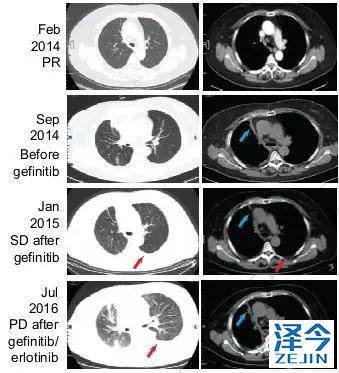

化疗,一代TKI治疗后,病情依旧进展

患者先进行化疗,基因检测显示为EGFR 19号外显子缺失,开始使用一代TKI药物治疗。一代TKI耐药后,发现患者出现T790M突变。

奥西替尼AZD9291治疗,病情稳定一段时间后,继续进展

因此,患者开始接受每日80mg的奥西替尼AZD9291治疗,患者在一个月内达到了病情稳定(SD),CA125水平迅速下降,经过8个月的无进展生存期,患者肺左下叶出现新的病灶,胸腔积液增多,病情发展。